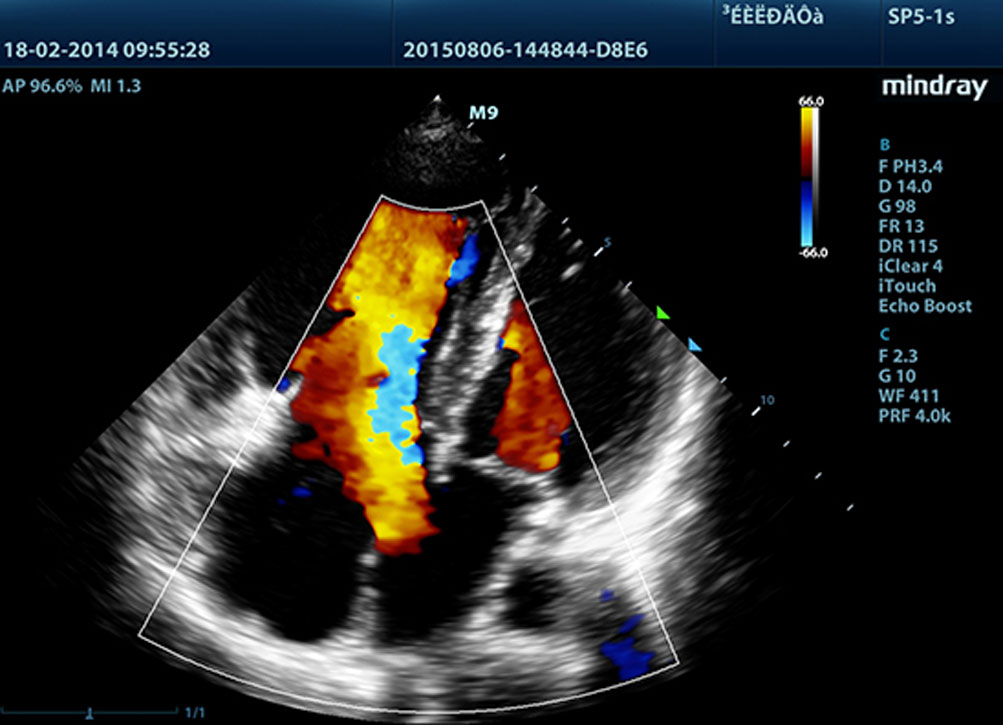

Dank Mindrays Ultraschallplattform der neuen Generation, mQuadro, hat das M9 den Branchenstandard auf ein bislang unbekanntes Niveau gehoben. Fortgeschrittene Signal├╝bertragung und ebensolche Empfangsprozessoren bieten hochsensitive, genaueste Echoerkennung. Innovative Schallkopftechnologie sorgt f├╝r bessere Penetration, h?here Aufl?sung und eine entsprechend einfachere Diagnose.

F├╝r sch?rfere Bilder sind alle mit dem M9 kompatiblen Sonden mit Mindrays einzigartiger 3T-Schallkopftechnologie ausgestattet. Das durch die Einkristalltechnologie verbesserte M9 bietet bessere Penetration und dynamischen Farbfluss, insbesondere bei der Untersuchung schwieriger Patientinnen oder Patienten.

LVO mit Belastungsechokardiographie

Die au?ergew?hnlichen F?higkeiten des M9 erlauben eine LV-Eintr├╝bung unter Belastung und verbessern die Visualisierung der Endokardoberfl?che durch bessere Unterscheidbarkeit von Myokardgewebe und Blutpool. Die Belastungs-Echo-Funktion des M9 umfasst ein ganzes Paket pharmakologischer Belastung verschiedener Belastungs-Echo. Das Paket wird durch ein flexibles Berichtssystem?unterst├╝tzt, das gem?? Ihren individuellen Erfordernissen optimiert werden kann.